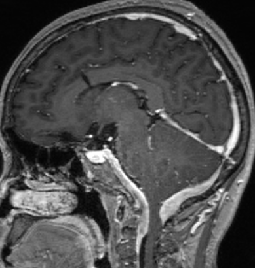

2013-5-16 MRI